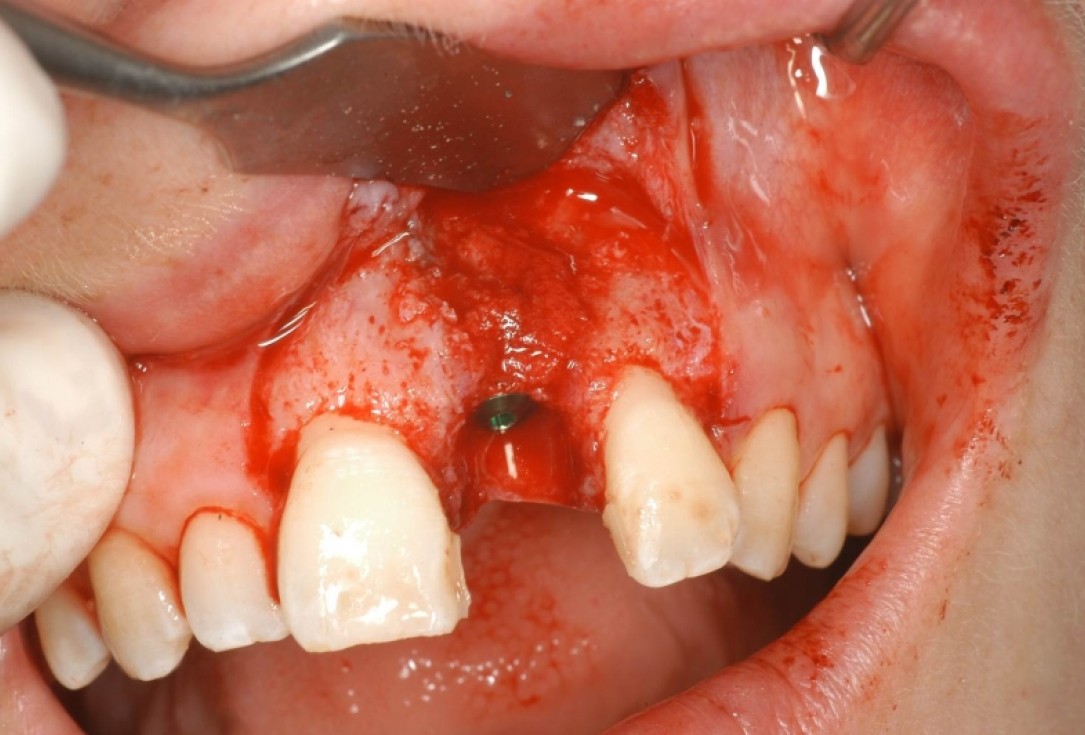

04/12 - Implant with extended dehiscence defectTreatment of dehiscence defect with cerabone® & Jason® membrane - Dr. M. Steigmann

05/12 - Covering of implant with autologous bone chipsTreatment of dehiscence defect with cerabone® & Jason® membrane - Dr. M. Steigmann